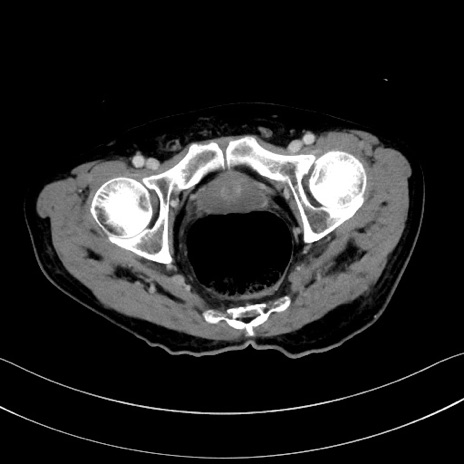

冠状断像

【症例】60歳代男性

【現病歴】胃癌にて胃全摘後。食思不振が悪化し、夜中に嘔吐することがある。

【既往歴】胃癌、胃全摘、脾摘、胆摘後